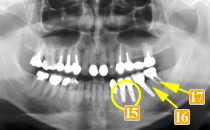

47歳男性

初診時、左下奥から3番目の歯(

)は、根に膿の袋ができており、歯が割れている可能性がありました。

この時点で抜歯の可能性が高いケースでした。

-

しかし

は何とか残したいということで“再植術”を行いました(

)。

(抜いて根の治療をした後に再度植えました。)

は初診時同様ブリッジとして使うには負担が大きすぎてすぐダメになってしまうと判断し、この歯を何とか残すために歯のない部分はインプラントという治療法を選択しました(

)。これならつながないでいいですし、インプラントでも噛む力が負担できるので他の歯を守れます。

さらに、

に関しても抜歯適応と思われましたが、何とか残すため“再植術”を行いました。

44歳男性

初診時、左下の奥歯が腫れて治療を繰り返している、全部白いもので治したい、とのことで来院されました。

左下の奥から2番目の歯(

)は、根の先に大きな膿の袋ができており、骨の吸収も著しいので残すのは難しいと判断しました。他の歯科医院では、抜いて、前後6本つながったブリッジか入れ歯になると説明を受けたとのことでした。

根の先に大きな膿の袋

歯がなく前後の2本で4本分を支えるブリッジの形になっています。

ブリッジだと残りの歯に負担がかかり、支えとなる歯がだめになってしまう可能性があり、入れ歯はご本人も気が進まない、また、バネをかけた歯にやはり大きな負担がかかることを考慮して、当院ではインプラントという選択にいたりました。

まず先に、前2本のインプラントを植えて噛みあわせを確立(

)。噛みあわせができたところで抜歯し、その後第一大臼歯へインプラント埋入しました(

)。骨の厚みが少ないので、傾斜させて埋入し、同時に骨移植も行いました。

1番奥の歯(レントゲンでは

)を利用してブリッジにしていたら、この歯はすぐに悪くなったことでしょう。

インプラントという選択を行ったことによって予後に不安があった歯を守ることができました。